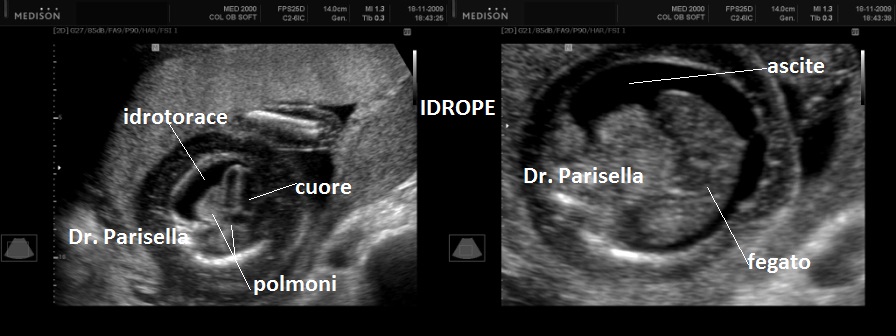

Possono essere presenti: idrope, cardioaptie congenite, labiopalatoschisi, oligoamnios, anomalie genito-urinarie, anomalie gastro-intestinali, anomalie del SNC.

La MICROMELIA SEVERA e l’ IPOPLASIA TORACICA SEVERA (legata al torace stretto con coste corte) sono i segni principali che indirizzano verso una corretta diagnosi. La POLIDATTILIA, sempre presente, è di tipo postassiale ed interessa sia mani che piedi. Spesso è presente idrope.

Sono presenti labiopalatoschisi, anomalie genitourinarie ed anomalie gastrointestinali. Può essere presente idrope ed ascite.

5)    L’ idrope può essere presente nei tipi I e IV.